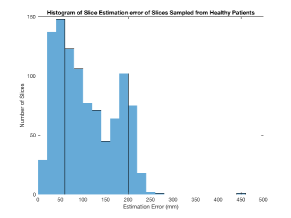

We use Siddon-Jacobs ray tracing [15] to generate Digitally Reconstructed Radiographs (DRRs) from the above described data. For training, we equally sample DRRs on equidistant half-spheres around 51 CT volumes at distances of 80cm, 60cm, and 40cm, between and around all three co-ordinate axes. For validation, we generate 1000 DRRs with random rotation parameters within the bounds of the training data at 60cm distance from the volumetric iso-centre. We trained on healthy volunteer data and tested on nine healthy and ten randomly selected pathological volumes (eight lung cancer and two spinal pathologies). Our approach is able to predict DRR transformations relative to the trained reference co-ordinate system with an average translation error of 106mm and plane rotation for healthy patients, and 130mm and average error for pathological patients. An example is shown in Fig. 4e,f. Note that these values are good enough to robustly initialize intensity-based registration refinement. SVRNet prediction can be improved by generating a denser training data set, in particular, in more equidistant half-spheres.